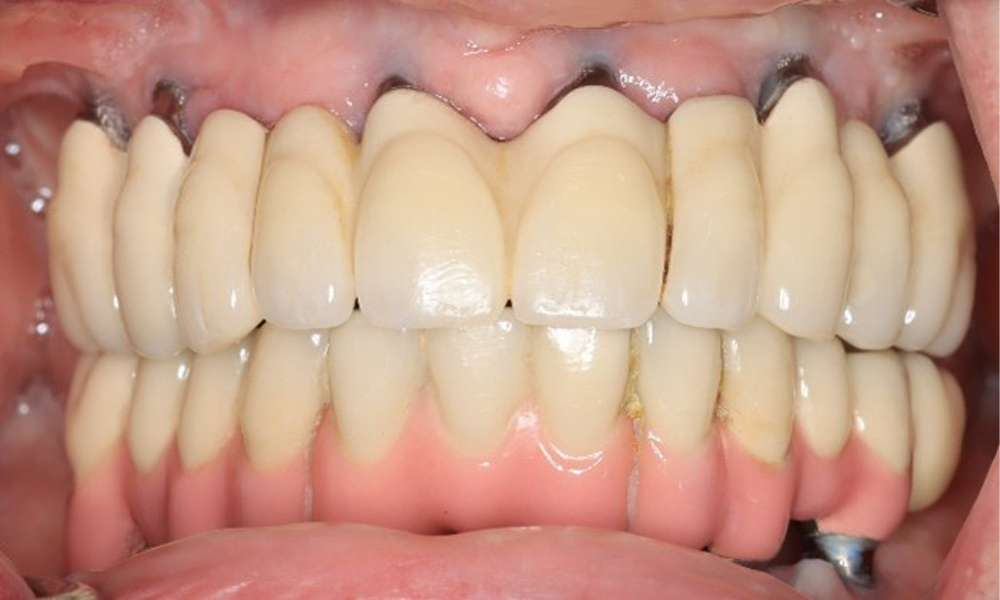

Front view of dentition (upper and lower jaw)

Figure 3: Frontal view